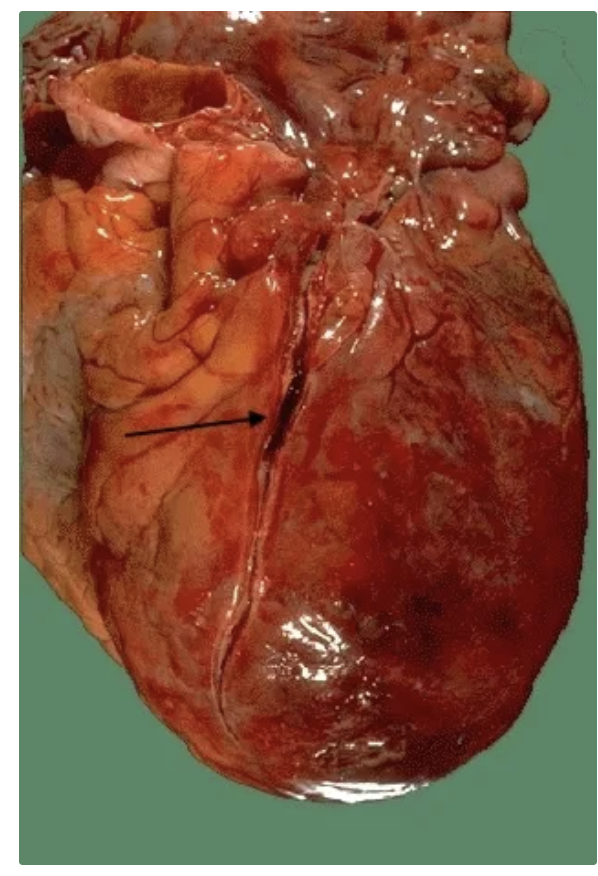

Cardiopatía isquémica crónica